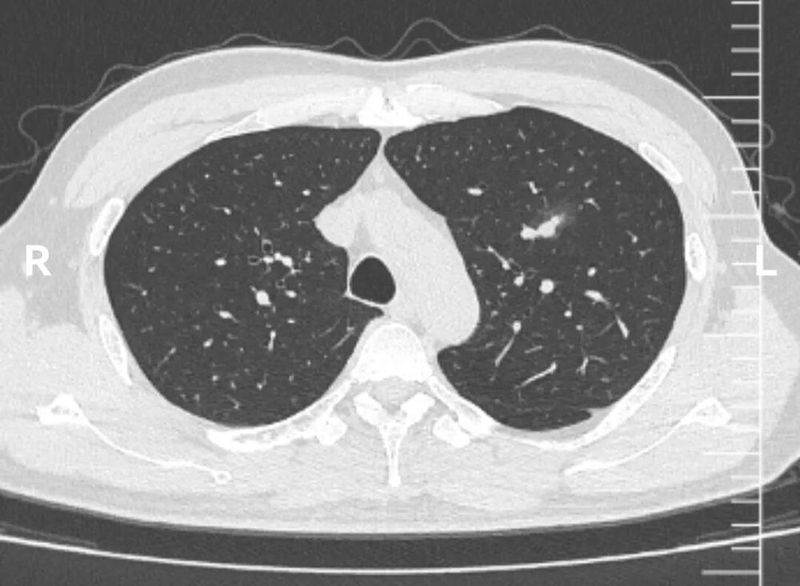

1个月后复查CT,该结节如愿明显吸收。